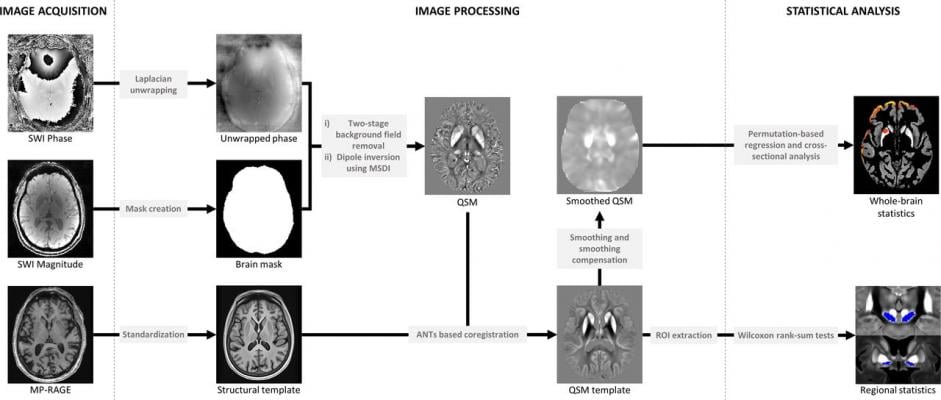

Summary steps of the processing pipeline for QSM reconstruction (phase pre-processing and map estimation) and whole brain/regional analysis. ANTs, advanced normalisation tools; MP-RAGE, magnetisation-prepared, 3D, rapid, gradient-echo; MSDI, multi-scale dipole inversion; QSM, quantitative susceptibility mapping; ROI, region of interest; SWI, susceptibility weighted imaging.

In the current study, researchers used a new technique, called quantitative susceptibility mapping, to map iron levels in the brain based on MRI scans. They found that iron accumulation in the hippocampus and thalamus brain regions was associated with poor memory and thinking scores. Iron in the putamen brain region was associated with poor movement scores, suggesting a more advanced stage of the disease.